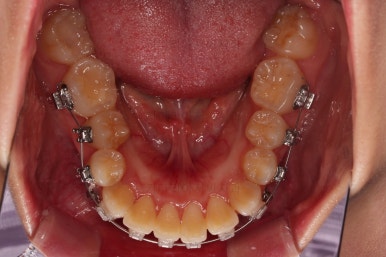

교합, 과개교합 모두 좋아졌고요.

발치 공간도 깔끔하게 닫히고 종료했습니다.

이제 부산무턱교정치과 전후 비교해 볼게요.